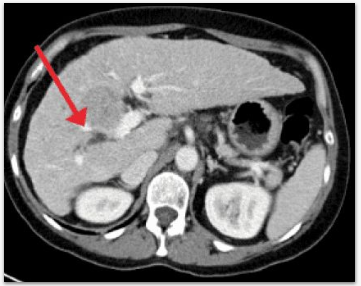

Triagem de exames de tomografia para priorizar casos suspeitos de lesões hepáticas.